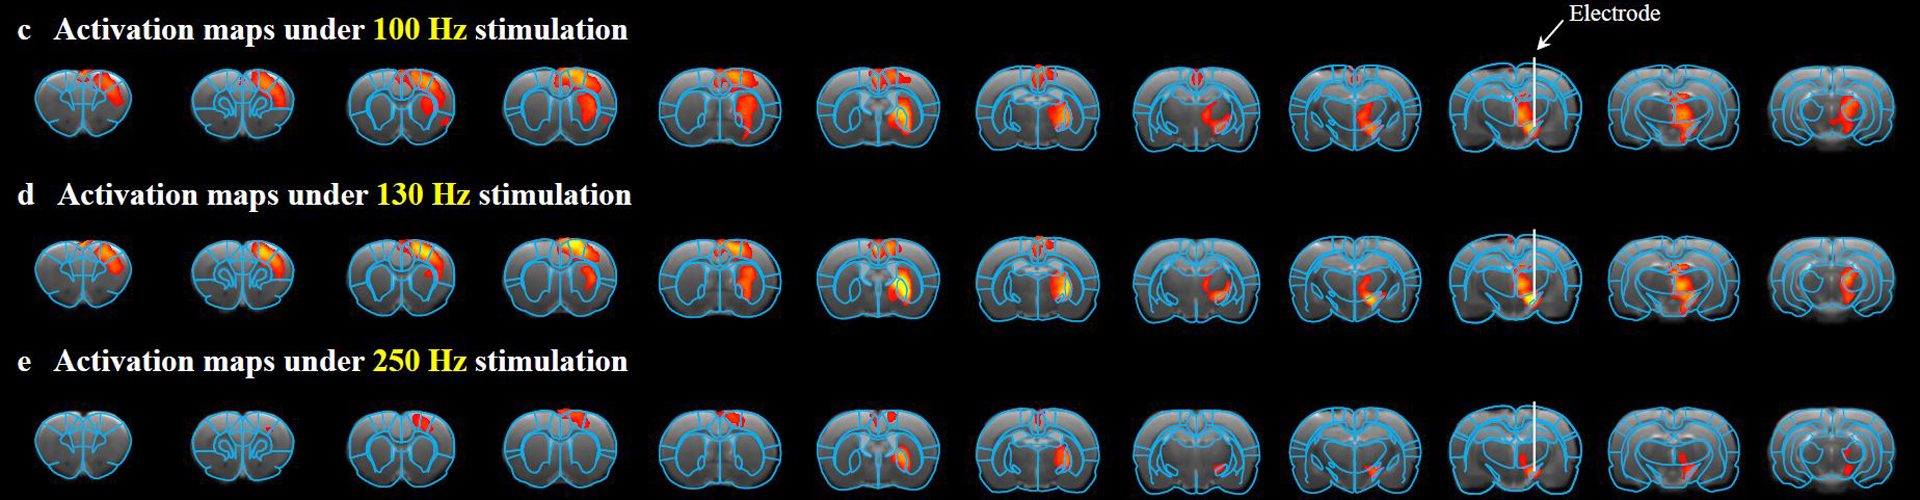

与磁共振高度兼容的电极促进解析深部脑刺激治疗机理

脑影像图1